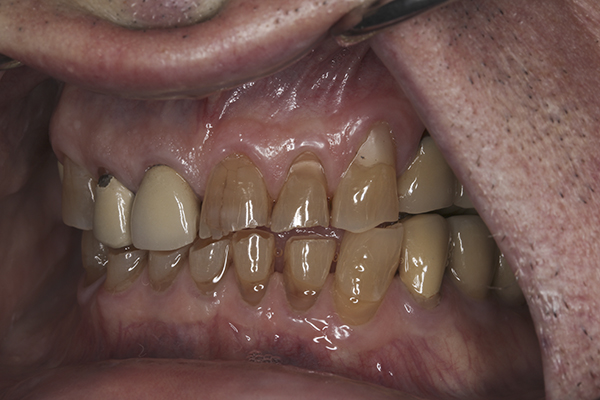

(7.) Preoperative anterior, open view. Note the significant amount of wear, erosion, and abfraction lesions.

Figure 7

(10.) Preoperative anterior, closed view. Note the end-to-end occlusion of the anterior teeth and the wear on the incisors and centrals resulting in no anterior or canine guidance.

Figure 10